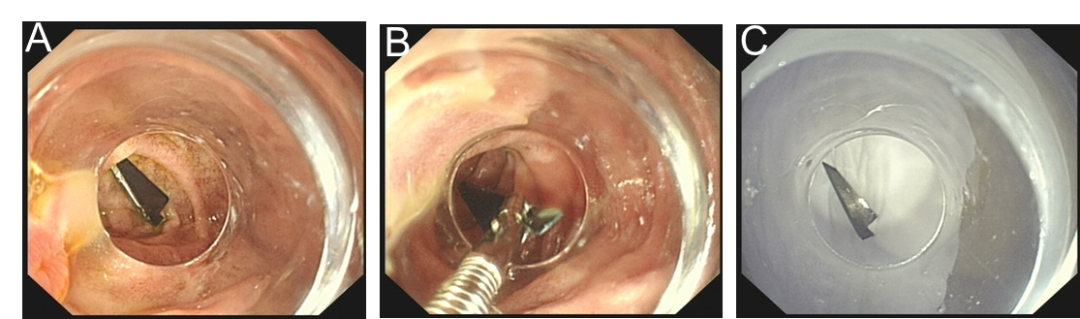

1月3次住院!61岁男性反复发热腹痛,竟揪出百万分之一的罕见消化疾病

病史摘要:61岁男性患者,因反复发热和右上腹痛1个月内3次住院。首次因发热、右上腹轻度疼痛入院,血培养检出大肠埃希菌;第二次出院4天后因高热、右上腹轻度疼痛再次入院,血培养仍为大肠埃希菌;第三次出院3天后因高热、右上腹痛加重入院,血培养依旧是大肠埃希菌。 诊疗过程:首次及第二次入院均用哌拉西林 - 他唑巴坦治疗,第三次入院实验室检查炎症指标变化大,血培养仍为大肠埃希菌